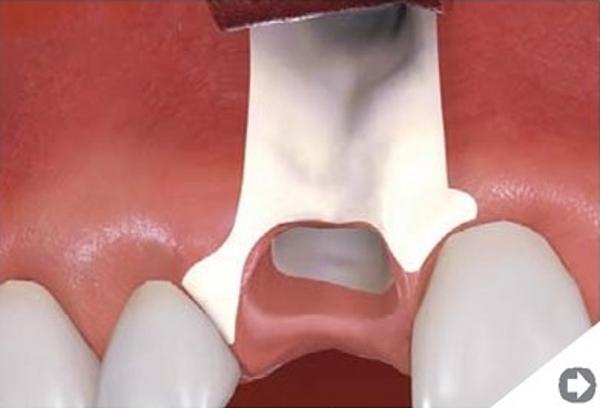

Sterowana regeneracja kości. Poszerzenie wyrostka zębodołowego żuchwy.